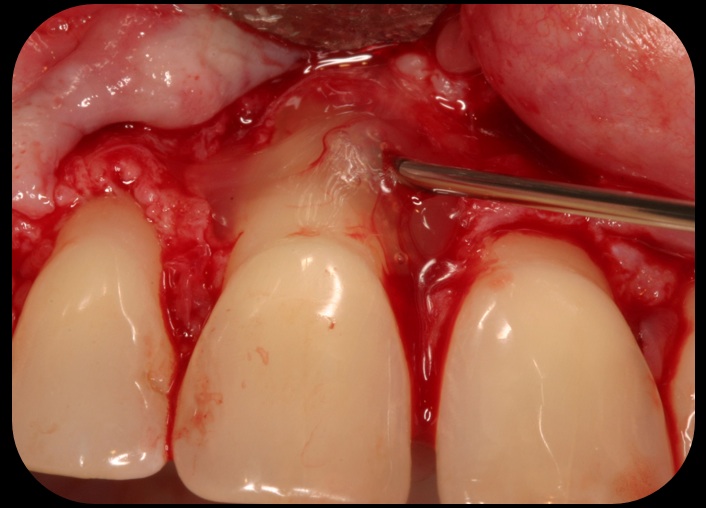

Then, too, are opportunities to prepare the site for regeneration by coupling therapies, applying an enamel matrix derivative, along with traditional bone grafts of demineralized freeze-dried bone allograft; potentially, gains in attachment with minimal probing depth and retained papilla may avoid the need for an implant (Figure 2 through Figure 7).

Severe periodontitis lesion.

Fig. 2

Facial bone loss and a mesial vertical defect.

Fig. 3

Application of enamel matrix derivative.

Fig. 4